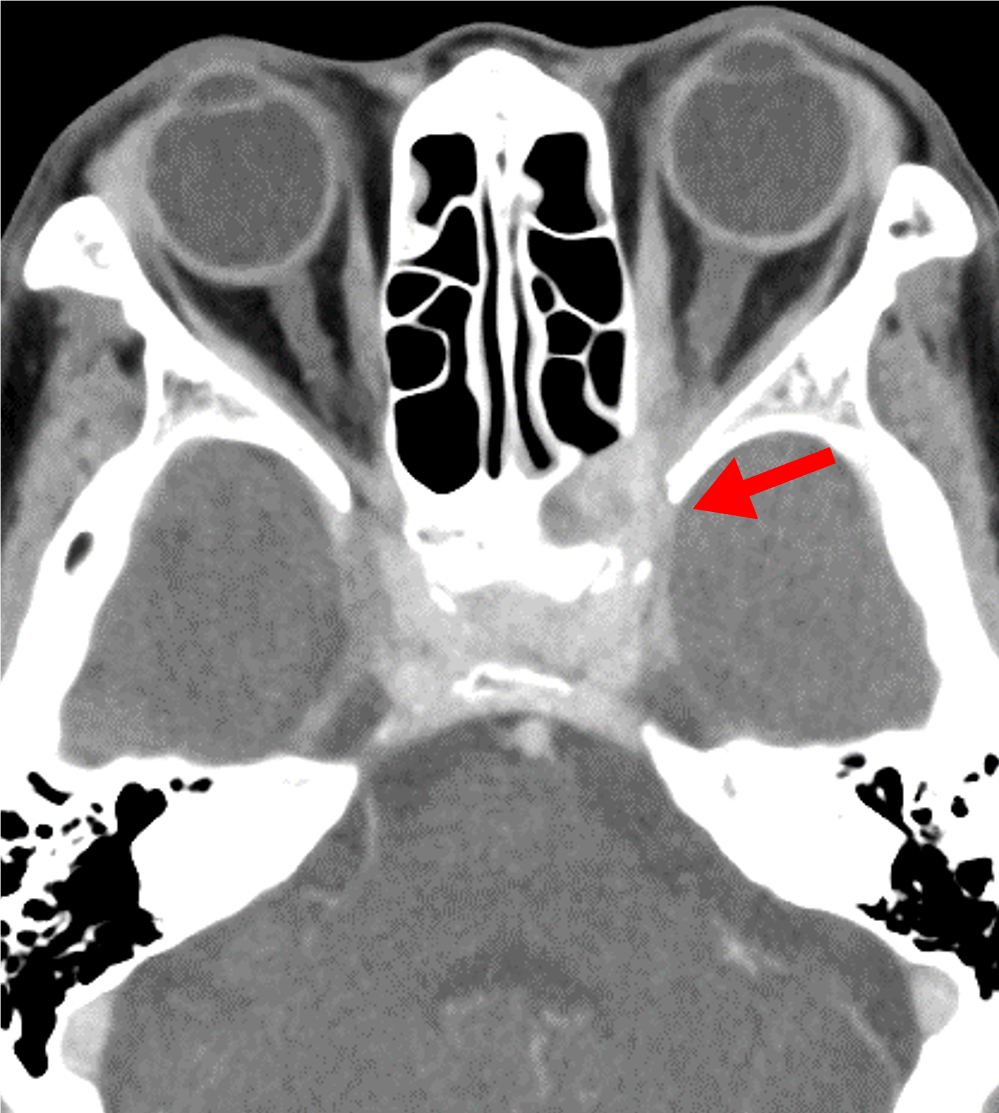

1か月前からの左眼痛、2週間前からの視野異常があり、前医で蝶形骨洞真菌症と診断された。視力障害の急速な進行と左内側視野欠損を来たしたため、当院に紹介された。造影CTにて左蝶形骨洞から左海綿静脈洞・眼窩尖部に浸潤する浸潤性真菌症を指摘された。緊急手術が施行され、病変から糸状様真菌が検出された。

急性浸潤性真菌性副鼻腔炎は臨床経過が4週間以内と急速に進行する病態を示す。骨破壊を伴って副鼻腔から眼窩・海綿静脈洞・頭蓋内に浸潤が見られる。また血管侵襲性が強く、時に仮性動脈瘤形成や動脈狭窄・閉塞、血栓形成を引き起こす。血管に沿って進展し、骨破壊を伴わずに副鼻腔外に炎症が浸潤する場合がある。

造影CTでは骨破壊の有無、副鼻腔外への炎症浸潤、また仮性動脈瘤や動脈狭窄・閉塞、血栓形成を評価する。海綿静脈洞は動脈性病変、静脈洞血栓、炎症浸潤が混在する可能性があり、早期動脈相・後期動脈相・平衡相を撮像することでこれらを鑑別する。

静脈の関与が少ない早期動脈相で動脈を評価するため、ボーラストラッキング法を用いた撮像を行う。一般的には総頚動脈や内頚動脈、中大脳動脈にROIをおいてモニタリングされることが多いが、本症例では海綿静脈洞の描出ができるだけ少ないタイミングで行うために、大動脈弓部にROIを設定した。また、海綿静脈洞の評価の際、静脈の濃染があり、炎症性組織の濃染がないタイミングでの評価を行うため、静脈相ではなく後期動脈相を撮影している。平衡相での濃染の有無で炎症性組織と静脈洞内血栓の鑑別が可能である。